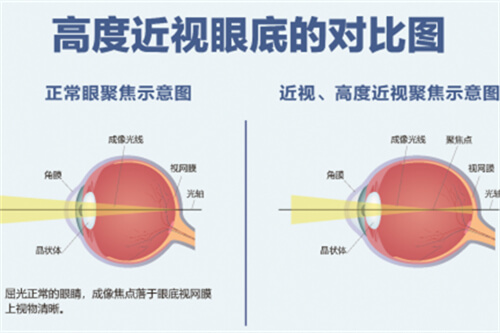

高度近视,特别是达到1500度的情况,对于患者而言,不仅影响生活质量,还可能带来一系列眼部健康问题。因此,许多患者关心的问题是:高度近视1500度能否通过手术进行治疗?本文将围绕这一问题进行详细探讨。

对于高度近视患者而言,眼底检查尤为重要。因为高度近视往往伴随着眼底病变的风险,如视网膜变性、裂孔、黄斑区病变等。如果患者的眼底情况不稳定或存在重度病变,可能需要可靠行干预治疗,待眼底情况稳定后再考虑手术。